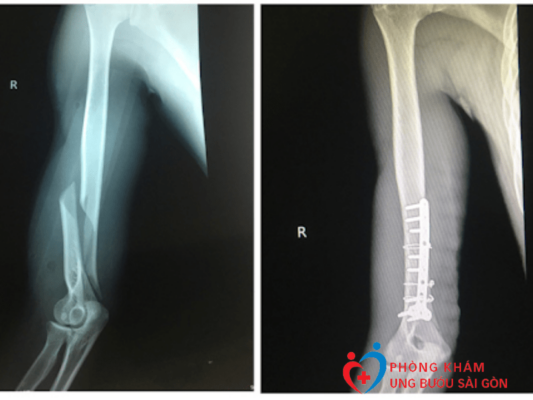

Kỹ Thuật Chụp X Quang Xương Cẳng Tay Thẳng Nghiêng Mà Bạn Nên Biết

Chụp X-quang xương cẳng tay là kỹ thuật được áp dụng phổ biến để chẩn đoán các chấn thương và bệnh lý ở cẳng tay, chẳng hạn như gãy xương, trật khớp,...